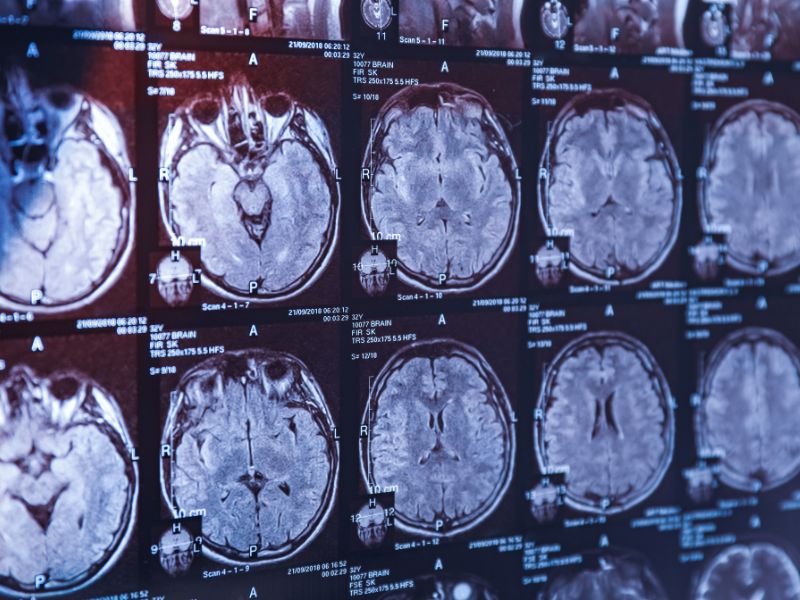

A concussion is a form of mild traumatic brain injury (TBI) caused by a blow, jolt, or bump to the head, disrupting normal brain function.

Symptoms can range from headaches and brain fog to memory loss, fatigue, anxiety, and mood changes — sometimes lasting weeks, months, or even longer.

More serious TBIs can result in lasting physical, emotional, and cognitive challenges, making early intervention crucial.